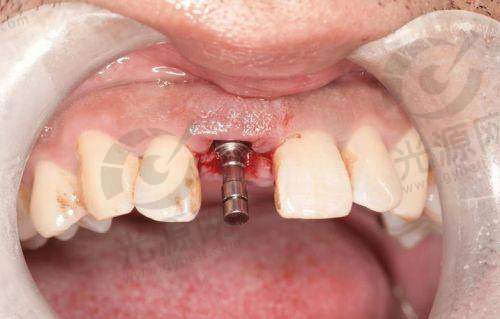

2. 种植牙:依据品牌与材料选择,价格从4599元 - 17000元都有。